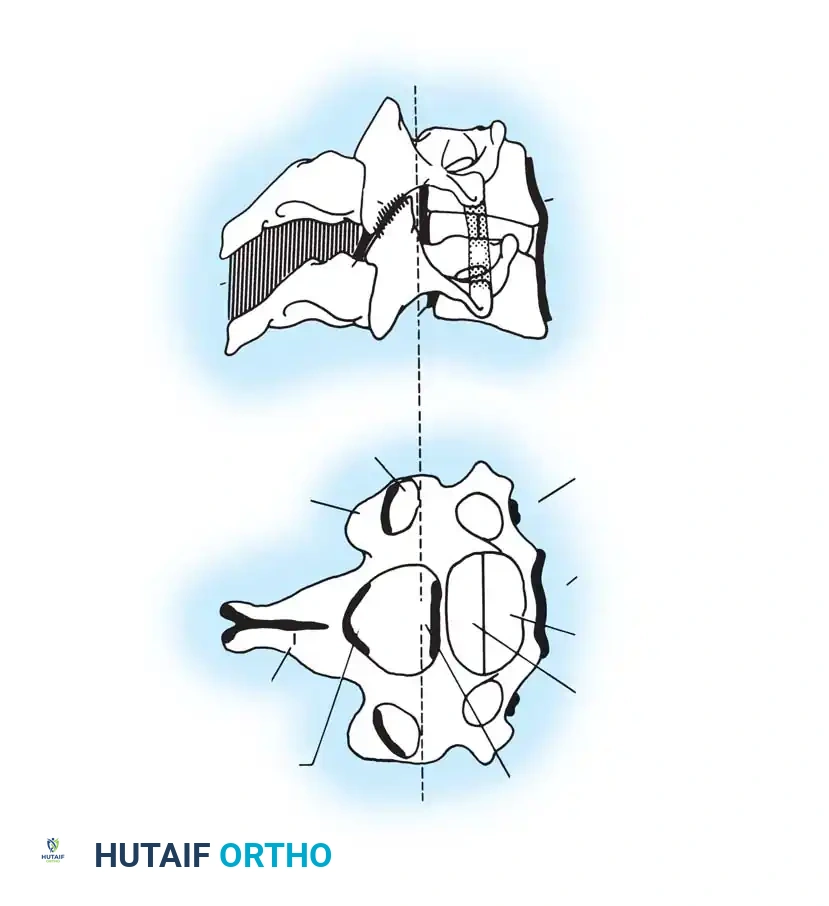

Fig 1. Important anterior and posterior supporting structures of the cervical spine. Understanding the integrity of the anterior longitudinal ligament, annulus fibrosus, and posterior ligamentous complex is paramount.

Fig 2. Diagrammatic representation of facet subluxation and dislocation mechanics.